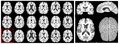

- Project week 2009 in Utah: we have developed/implemented HAMMER registration algorithm using ITK classes. New ITK classes have been created for tasks of HAMMER. Each component has been tested. The source code is version controlled at NITRC site. The current development corresponds to the original Hammer algorithm that is based on tissue classification of T1 weighted images (as outlined on the first HAMMER paper).